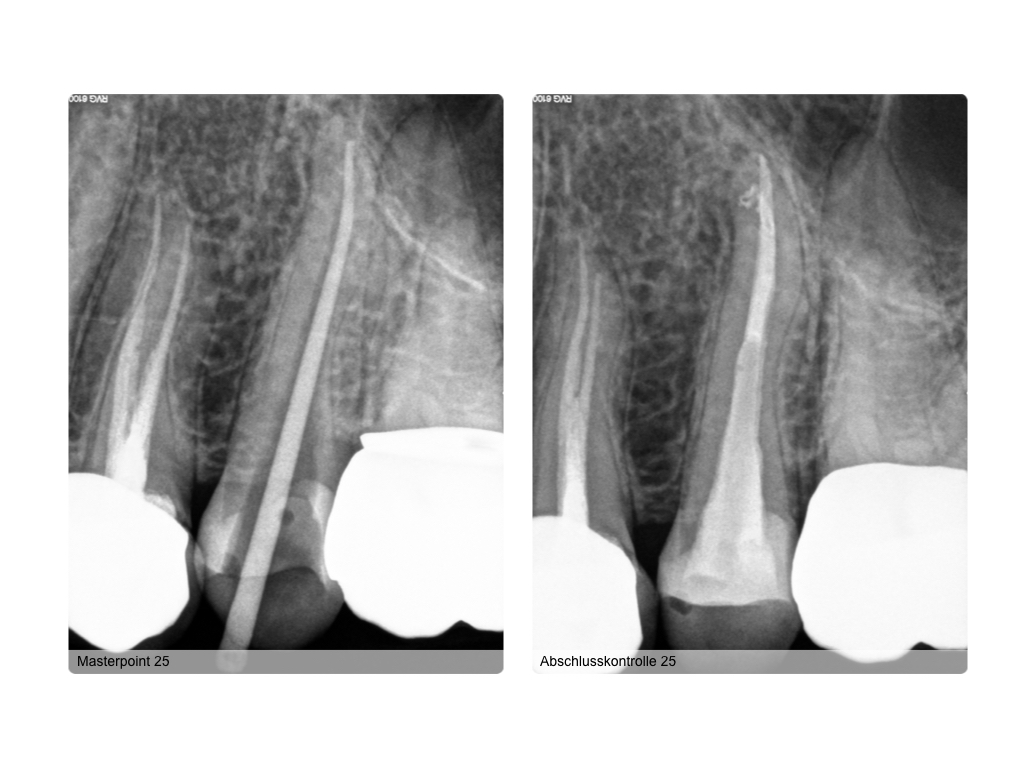

WS15_11.009 Veröffentlicht 3. November 2015 am 1024 × 768 in Fistel mit unklarer Ursache – 2D versus 3D